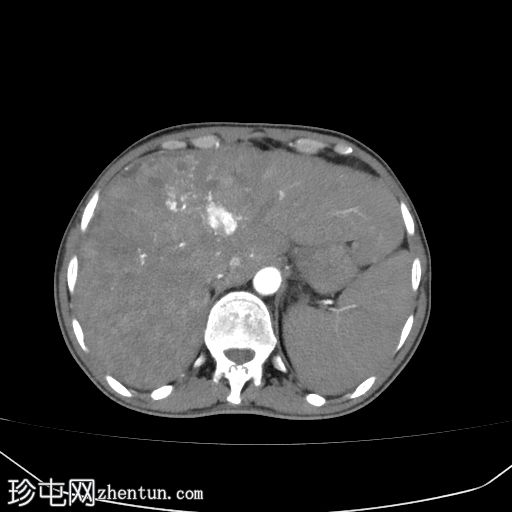

腹部(肝脏)CT

轴位

轴位增强扫描

动脉期

肝硬化征象包括表面和实质结节、实质异质性、右后肝切迹征和容积重分布。

门静脉可见肿瘤血栓,表现为血栓强化。

肝脏可见无数细小病灶,动脉期呈非环状强化,门静脉期呈消退,提示弥漫性肝细胞癌。

其他发现包括腹水和左侧肾上腺可疑增厚。